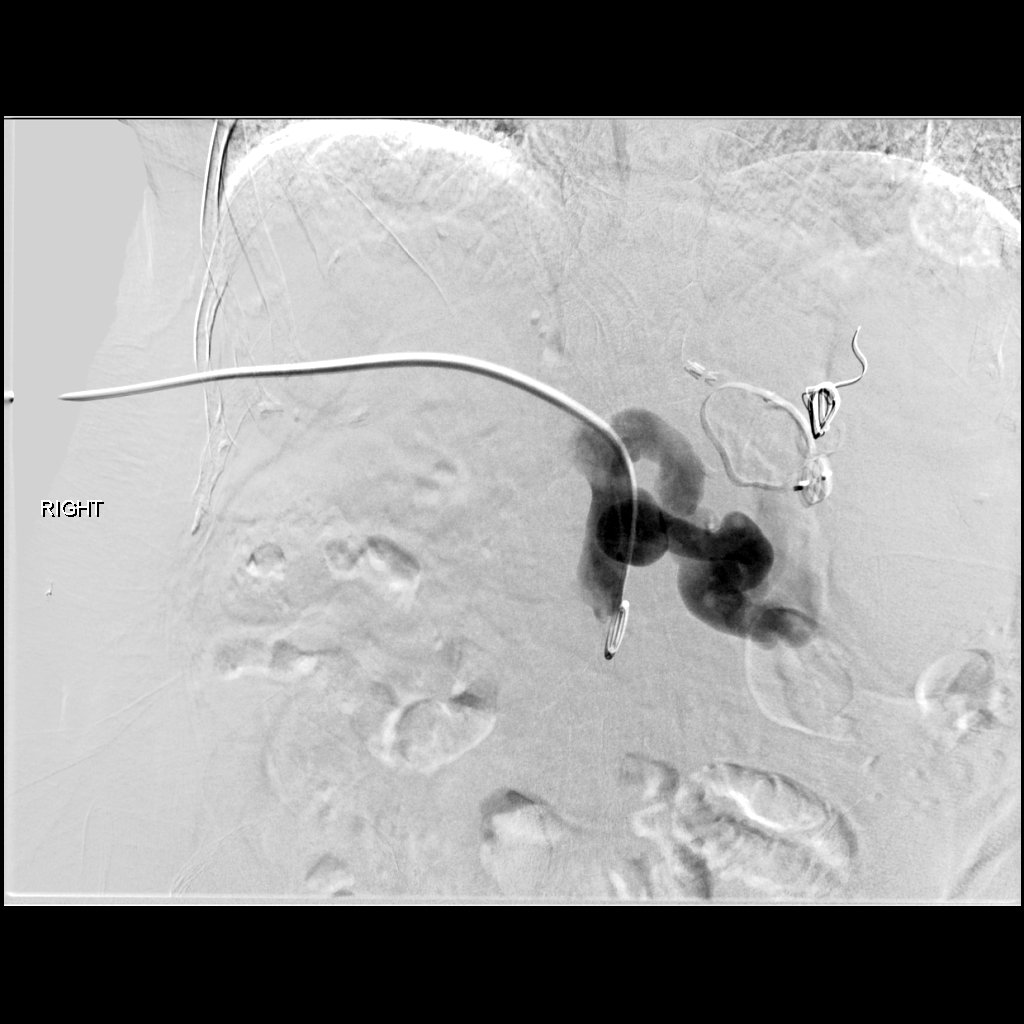

47 yo p/w massive PE s/p systemic tPA and persistent hypotension. Extensive right-sided PE on angio. Thrombus completely removed with FlowTriever mechanical thrombectomy. PA pressure decreased to 30mmHg from 64 mmHg immediately. #IRad @SIRspecialists @SIRRFS @SIR_ECS @JVIRmedia